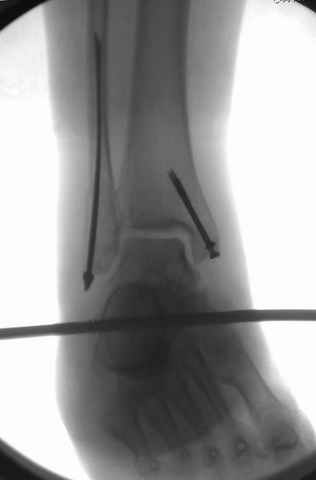

Pilon fracture:

конец малоберцевой кости, к нему прикрепляется латеральный суставной фрагмент дистального эпиметафиза большеберцовой кости (как на снимке)

и таранная кость, которые при репозиции малоберцовой кости репонируются автоматически.

За последнее 10-12 лет после стабилизации малоберцовой кости, стали применять более усовершенный, сложный, хорошо вам известный метод

Илизарова (кстати наряду с тибиал плато, пилон является одним из показанием по применению аппарата Илизарова при травмах) или Hybrid

Fixator, из минимальных доступов комбинированный метод для восстановления суставной поверхности-фиксация каннулированными

шурупами, создания жесткой системы фиксации до сращения перелома, защита от вальгусной деформации и на место образовавщегося метафизарного дефекта- костная пластика ауто костью или его

синтетические заменители, это сегодняшная тактика лечения.